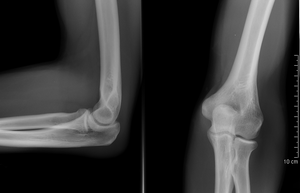

المرفق إنگليزية: Elbow هي عظمة مفصلية تربط عظمة العضد مع عظمتي الزند و الكعبرة. وتكون أماكن الالتقاء الثلاثة، ثلاثة مفاصل أصغر وتسمح هذه المفاصل الصغيرة بحركات معينة، حيث يسمح مفصلا العضد ـ الزند والعضد ـ الكعبرة للشخص بثني الساعد إلى أعلى وأسفل، بينما يسمح مفصلا الكعبرة ـ الزند والعضد ـ الكعبرة بدوران الساعد وكذلك راحة اليد أعلى وأسفل.

يحيط بمفصل الكوع كبسولة من نسيج متين. وتقوم هذه الكبسولة مع عدد من الأنسجة القوية الحبلية الشكل التي تُعرف بالأربطة بالمحافظة على العظام في أماكنها. ويعمل السائل الزيلي بمثابة مزلق لتقليل الاحتكاك عند الكوع.

أجزاء مشتركة

| Joint | From | To | Description |

| humeroulnar joint | trochlear notch of the ulna | trochlea of humerus | Is a simple hinge-joint, and allows of movements of flexion and extension only. |

| humeroradial joint | head of the radius | capitulum of the humerus | Is a hinge-joint joint. |

| proximal radioulnar joint | head of the radius | radial notch of the ulna | In any position of flexion or extension, the radius, carrying the hand with it, can be rotated in it. This movement includes pronation and supination. |